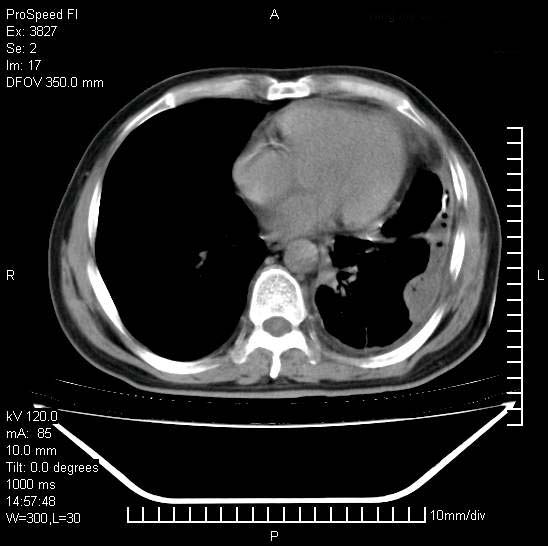

男性,一月前出现右侧肋区疼痛,较剧烈,干咳,无发热,自诉使用抗炎药后缓解,几天前又出现左侧剧烈疼痛,

发热,体温38。9,今天ct,考虑左侧包裹性脓胸,胸腔积液,右上中肺小斑片影,结核/炎症?胸水未见恶性细胞。